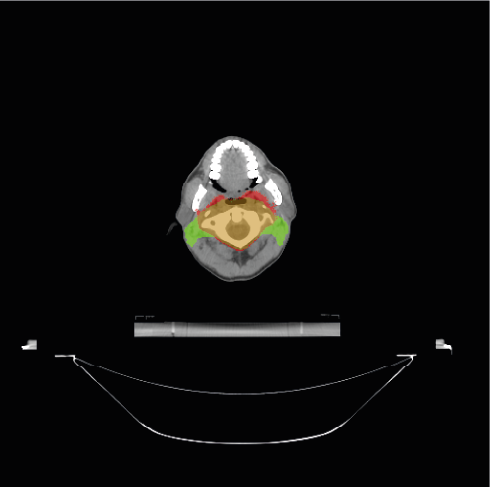

To further understand the areas where the models do not accurately segment the PTV, we provide some visual examples of the poor segmentations Figure 4. The first row of the Figure 4 shows four examples of slices poorly segmented by the BCEL model. The first slice (Figure 4a) corresponds to the head and neck area. The segmentation error in the left and right areas of the head (i.e., the green areas) may be due to conservative segmentation of the second level of neck lymph nodes in the ground truth. The standard reference point for segmenting these lymph nodes might be a slightly higher slice, but the radiation oncologist likely included the target on this slice due to the large CT thickness of 5 mm. The second slice (Figure 4b) shows an absence of hepatic portal lymph nodes. This area is subject to high anatomical variability, and due to the lack of contouring guidelines [38] in the early years of data acquisition, this area was often omitted by the radiation oncologist. In the third slice (Figure 4c), the absence of the pre-sacral lymph nodes (anterior to the sacrum) is evident. Moreover, the predicted segmentation of the external iliac lymph nodes is inaccurate. This target area is defined by adding a margin to the iliac vessels. In the fourth slice (Figure 4d), representing the legs area, the prediction fails to segment the inguinal lymph nodes, likely because these are frequently omitted by physicians. The second row of the Figure 4 shows the same slices overlayed with the predictions of the DL model. Notably, the segmentation errors of the DL model closely resemble those of the BCEL one, previously discussed. Please notice that the segmentation mistakes of DL model are very similar to the ones of the BCEL model, previously discussed. Nevertheless, a higher propensity for false negatives is discernible in the DL model’s segmentations, evidenced by the larger green regions surrounding the bones in Figure 4h and within the iliac lymph node area in Figure 4g.